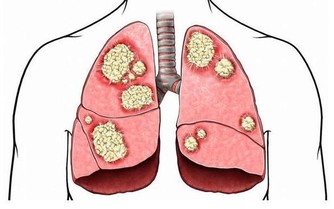

統計發現,很多胰腺炎尤其是急性胰腺炎的發病,都與不健康的飲食習慣有關,比如暴飲暴食、食用變質食物等。特別是蛋白含量高的剩魚、剩肉變質後,也可能導致細菌感染,進一步誘發胰腺病變。